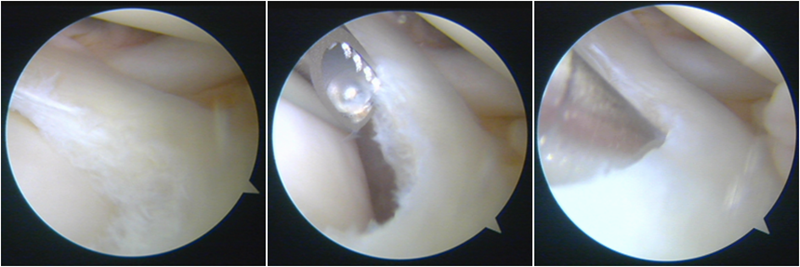

股骨侧保残骨道建立

股骨侧骨道建立,椭圆形扩孔保残9mm

韧带导入过程